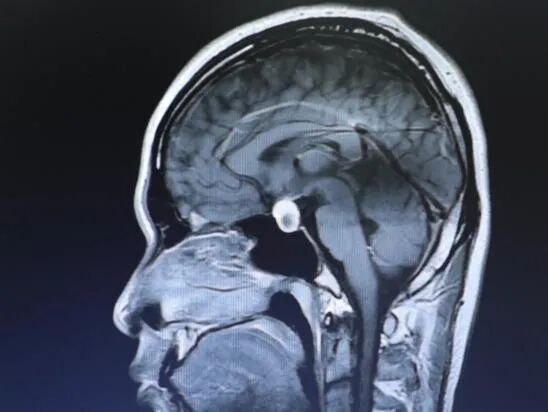

成人用户 右侧植入SYNCHRONY人工耳蜗

核磁检查原因:耳蜗术后进行垂体瘤检查

从影片看患者的垂体瘤近期有出血和生长的情况,目前需要进一步完成其它相关检查,再评估是否需要手术。